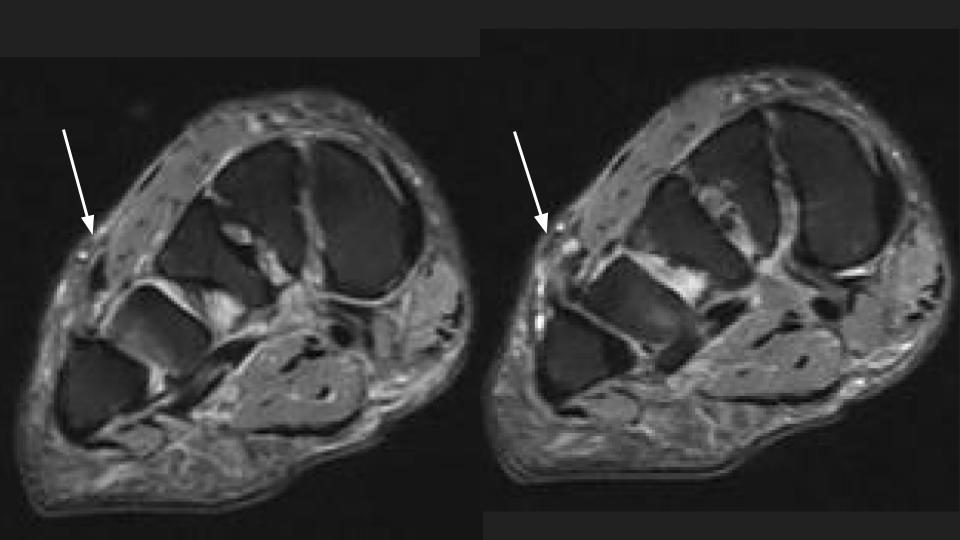

Figure 3 for case peroneus tertius ( RID2915 )

Figure 3

Area of pain indicated by markers surrounds the insertion of the Peroneus Tertius tendon onto the base of the 5th and likely also 4th dorsal MT base. The tendon is thickened with intrasubstance intermediate T1 and bright T1 signal. This is the insertional tendinosis of the peroneus tertius, with probable superimposed partial intrasubstance insertional tear suggested in the Sag fat sat images. The reference does not say much about the insertion, but includes some anatomic references that indicate variation in the insertion site at the 5th and sometimes 4th and 5th MT base. Reference article.